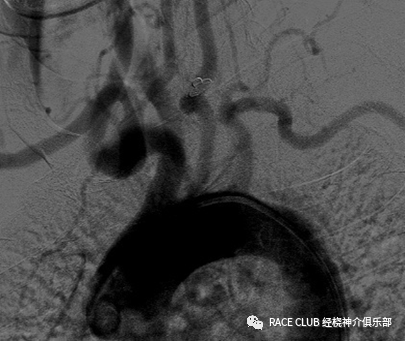

弓上造影(经桡动脉)

1.做完弓上造影边后撤猪尾导管,边旋转,头端朝向左侧成“6”字型

2.进260cm导丝入降主动脉至腹主动脉

3.稳住导丝,撤掉猪尾导管

造影导丝是什么全脑血管造影术_https://www.jmylbn.com_新闻资讯_第25张

4.沿导丝送入西蒙导管,至大弯完全进入降主动脉

5.撤掉260cm导丝

6.退导管至大弯的顶点顶在弓上,边退边顺时针旋转导管

造影导丝是什么全脑血管造影术_https://www.jmylbn.com_新闻资讯_第26张

7.把导管转成“8”形

8.前推导管,导管头端会弹入左锁骨下动脉,稍回撤导管,让导管头端进入左锁骨下动脉,冒烟、摆体位,造影

9.左锁骨下动脉造影完后,前推导管,导管弹入左颈总动脉,稍后退导管,让头端头端进入左颈总动脉,冒烟后,摆体位造影